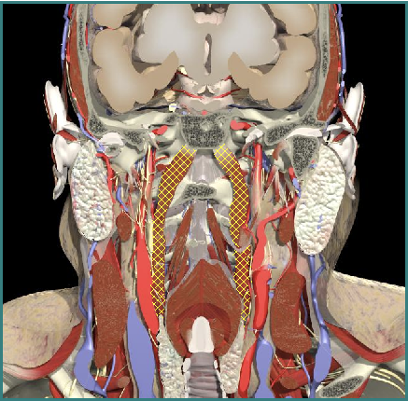

Laterocollis

Cervical Dystonia

Muscle Selection

Larynx shifted relative to sternum

Laterocaput

Movement in the Coronal Plane

Majority of patients (60%) have lateral flexion of head and neck in varying proportions.

20% head only, 20% neck only

Muscles Attached to Skull

Trapezius

Sternomastoid

Splenius capitis

Splenius cervicus

Levator scapulae

Longissimus capitis